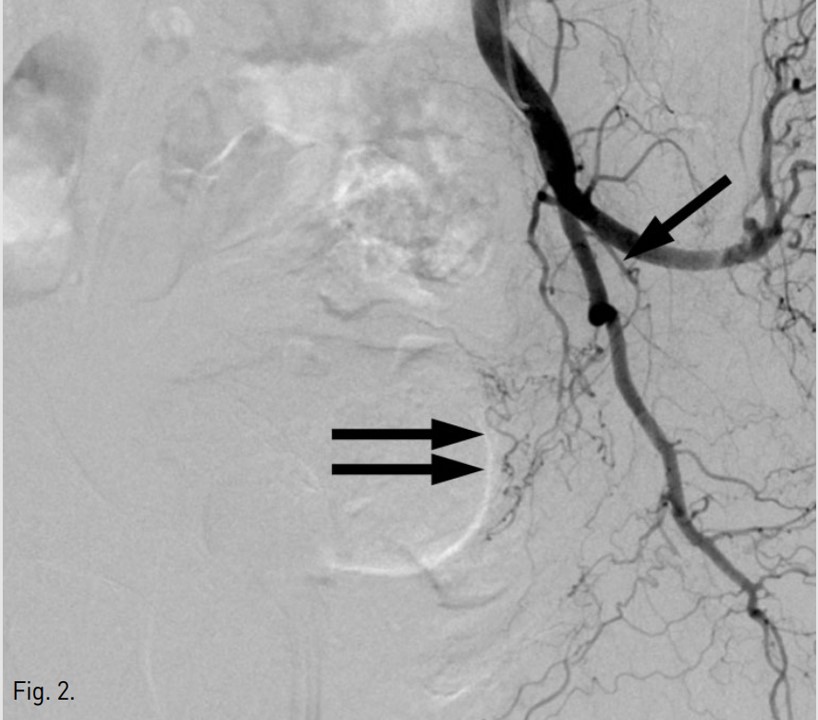

Fig. 3.

Fig. 3. Left vesical artery was embolized with gelfoam after superselection with a microcatheter.

우측 총대퇴동맥을 역방향천자하여 5F sheath(Terumo, Tokyo, Japan)를 삽입함. 5F Robert uterine catheter(Cook, Bloomington, USA)를 사용하여 좌측 내장골동맥을 선택한 후 방광에 삽입되어 있는 Foley catheter를 통해 10%로 희석된 조영제 100ml를 방광 내로 주입한 다음 동맥조영술을 시행함(Fig. 1, 2). 좌측 내장골동맥조영술에서 좌측 아래방광동맥이 두드러지게 커져 보여, 좌측 방광동맥을 미세도관(Progreat, Terumo, Tokyo, Japan)과 미세유도철사(GT wire, Terumo, Tokyo, Japan)로 superselection한 다음 gelfoam으로 색전하였음(Fig. 3). 색전술 시행 후 얻은 좌측 내장골동맥조영술에서 더 이상 방광동맥이 보이지 않았음(Fig. 4) 우측 내장골동맥조영술에서는 이상소견 보이지 않아 우측에서는 색전술을 시행하지 않음. 이후 환자는 혈뇨 증상이 호전됨.